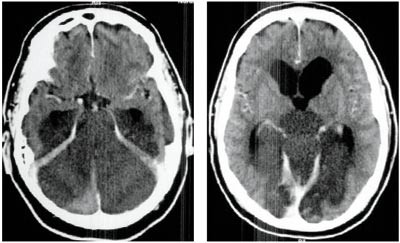

Ny cerebral CT ca. 25 timer etter hendelsen viste utbredt infarsering av hjernestamme, cerebellum og begge oksipitallapper samt begynnende hydrocephalus (fig 3). Gransking av arkografiundersøkelsen viste ingen fylling av venstre a. vertebralis og bare en meget langsom fylling av sentrale deler av en tynn høyre a. vertebralis. Det var ingen kontrastfylling av a. basilaris (fig 2).

Angiography with contrast injected into the aortic arch showed preserved circulation in both internal carotid, middle and anterior cerebral arteries, but absence of basilar artery circulation. A cerebral CT scan was initially normal, but 14 hours later a new scan demonstrated infarction of the brain stem, cerebellum and occipital lobes. The Norwegian criteria for organ donation were not fulfilled as these require stop of all intracranial circulation. The respirator was disconnected and the patient died.